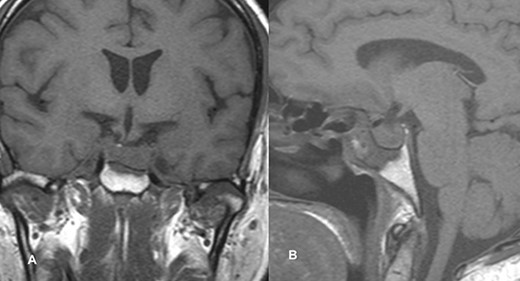

PA was diagnosed when radiographic findings showed acute pituitary hemorrhage and subsequent pituitary adenectomy was planned, but surgery was delayed up to 13 days because of non-critical coronary artery disease detected on coronary angiography. When his condition stabilized, he underwent surgery. The tumor was soft to firm and a safe maximal resection was performed. Hemostasis was achieved and sella packed with fat harvested from the subcutaneous fat of the abdomen. Postoperatively, he suffered transient diabetes insipidus, which was treated with desmopressin injections and resolved by day 5 postoperatively. He was then discharged on the 8th postoperative day. At the time of discharge, he had residual ptosis, which gradually improved over 2 weeks based on clinical assessment at the outpatient visit. He fully recovered from ptosis over a month. Postoperative imaging performed at 6 weeks showed a residual tumor measuring 1.9 × 1.5 × 1.1 cm with no significant mass effect on the cavernous sinus; therefore, he was referred to an oncologist for postoperative radiotherapy (Fig. 2).

Follow-up MRI imaging of case 1 showed the sellar, suprasellar residual lesion measuring 1.9 × 1.5 × 1.1 cm without a significant mass effect on cavernous sinus.